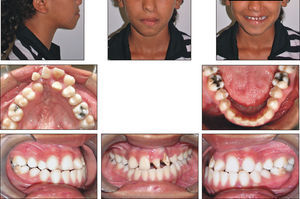

A paciente A, do sexo feminino, passou por procedimentos cirúrgicos condizentes ao protocolo de reconstrução da fenda labiopalatina na primeira infância, como queiloplastia, palatoplastia e faringoplastia12. Como esperado, houve redução da largura do arco dentário superior devido à junção dos segmentos e uma limitação no crescimento do terço médio da face. Aos 12 anos, em estágio pré‐puberal, CS1 de maturação óssea13, a paciente apresentava clinicamente um perfil côncavo, molares com padrão de oclusão em Classe I de Angle, atresia transversal maxilar severa na região anterior e mordida cruzada anterior (figs. 1 e 2). Pelo exame da telerradiografia em norma lateral da face, observou‐se a sugestão de estreitamento e constrição das vias aéreas, relação esquelética de Classe I (ANB=3,6°), mas apresentando uma tendência à Classe III (Wits=−3,3mm), maxila retroposicionada em relação à base do crânio (SNA=80,6°), bom posicionamento de incisivos superiores (1.NA=3,5mm; 1.NA=21,9°) e projeção vestibular de incisivos inferiores (1.NB=8,9mm; 1.NB=28,1°; IMPA=93,7°) (fig. 3). Como parte da documentação ortodôntica inicial para o planeamento do tratamento, que incluía os enxertos ósseos na região da fenda, a paciente foi submetido a uma tomografia computadorizada por feixes cônicos (TCFC), no tomógrafo i‐CAT (Imaging Sciences International, Hatfield, Pennsylvania, Estados Unidos da América [EUA)), com field of view (FOV) de crânio estendido (23cmx17cm), voxel de 0,3mm3, 36,90mA, 120kV e tempo de exposição de 40 segundos. Frente a todas as características encontradas, foi determinada uma maior necessidade de ERM na região anterior, em preparação para enxerto ósseo e tratamento ortodôntico corretivo. Após o diagnóstico, foi escolhido o expansor em leque. O aparelho foi confeccionado com um parafuso expansor em leque (Morelli, Sorocaba, São Paulo, Brasil). O aparelho possui bandas nos primeiros molares permanentes e uma dobradiça na região posterior, fixada em acrílico, de onde partem extensões de fio 0,9mm, apoiadas nas superfícies palatinas dos molares decíduos ou pré‐molares. Este aparelho é considerado dentomucossuportado (fig. 4).

O histórico de cirurgias do paciente B, sexo masculino, se assemelha ao da paciente anteriormente descrito, assim como os efeitos sobre sua maxila e suas características relativas ao perfil facial, padrão esquelético e dentário (figs. 5 e 6). Igualmente acompanhado pelo CENTRARE, concordou‐se em iniciar a ERM aos 12 anos. Realizados exames clínicos e TCFC, observou‐se: tendência a uma má oclusão esquelética de Classe III (ANB=0,6°; Wits=–2,1mm), maxila bem posicionada em relação à base do crânio (SNA=81,1°), incisivos superiores retroposicionados e retroinclinados (1.NA=‐1,5mm; 1.NA=11,6°) e incisivos inferiores bem posicionados na base óssea (1.NB=28,5 graus; IMPA=92,8 graus) (fig. 7). Diante da necessidade de expansão limitada à região anterior, foi instalado em JFRL o disjuntor mini‐Hyrax invertido com BTP11. Confeccionado com um mini parafuso (Variety Expander, DynaFlex, Saint Ann, Missouri, EUA) posicionado na região mais anterior possível do palato. Extensões provenientes do parafuso (fio 1,4mm) contornaram a superfície palatina dos caninos, passando pelas bandas nos primeiros pré‐molares e chegando até à superfície palatina dos segundos pré‐molares. Além disso, uma BTP (fio 0,9mm) foi soldada em bandas nos primeiros molares permanentes (fig. 8).

Discussão e conclusõesConsiderada a deformidade craniofacial mais prevalente, a FLP pode ser diagnosticada no primeiro trimestre de vida intrauterina, através de ultrassonografia14,15. O diagnóstico precoce favorece um planeamento adequado que, associado às novas técnicas cirúrgicas de tratamento reabilitador, reduz a severidade da constrição maxilar. Embora a evolução das técnicas venha acontecendo, os pacientes ainda necessitam de tratamento ortodôntico/ortopédico, como a ERM, que compensa a relação maxilomandibular aumentando a dimensão transversal da maxila6,16. Nos 2 casos clínicos aqui descritos, os pacientes haviam se submetido a queiloplastia e palatoplastia no primeiro ano de vida. Ambos desenvolveram perfil côncavo, atresia transversal maxilar severa e mordida cruzada anterior. O momento selecionado para executar a expansão maxilar e a correção da deficiência transversal foi o período pré‐puberal (CS1) de maturação esquelética. Espera‐se que, pela imaturidade óssea, ocorra a ruptura da sutura palatina mediana de maneira mais fácil, aumentando a eficácia da ERM13.